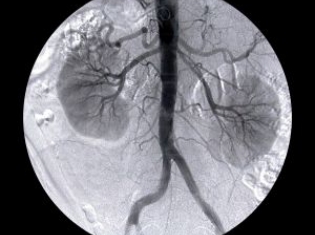

While there are well over a dozen different types of kidney cancer, a large study was launched on papillary renal cell carcinoma, sometimes abbreviated as pRCC, to make sure that data was looked at in a similar context.

Researchers from the University of Padua found that papillary renal cell carcinoma forms about 10 percent of kidney cancers, more commonly in men, with a fairly good prognosis for surgical treatment.

"Because papillary renal cell carcinoma (pRCC) only affects ten to 15 percent of kidney cancer patients, the small number of patients enrolled in individual studies makes it hard to draw meaningful conclusions about how the disease will progress" says lead author Dr Vincenzo Ficarra, associate professor of urology at the University of Padua, Italy.

Patient data was taken from 16 different surgical centers over a 12 year period. Out of 5,463 patients with kidney cancer, 577 were later found to have papillary renal cell carcinoma. Results of the surgery and treatment were followed for an average of 3 years.